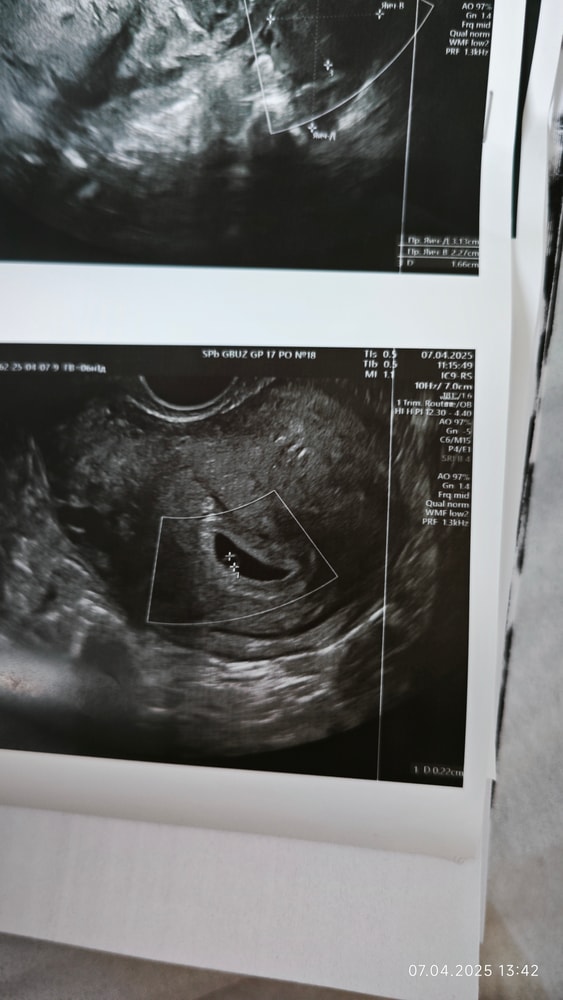

Ставят замершую беременность

Хгч 30.03.25 621,9 на узи ничего нет, хгч 01.04.25 1381 на узи плодное яйцо 4,5 мм. узи 03.04.25 плодное яйцо 7 мм, желточный мешок 1,3 мм , узи 07.04.25 плодное яйцо 9,5 мм желточный мешок 2,2 мм эмбриона нет, в режиме ЦДК внутри ПЯ зон кровотока нет, срок на 07.04.25 6 недель и 1 день. Плохой прирост плодного яйца за последние два узи и плодное яйцо неправильной формы, говорят замершая беременность. Может у кого-нибудь были похожие случаи, есть ли ещё шанс?